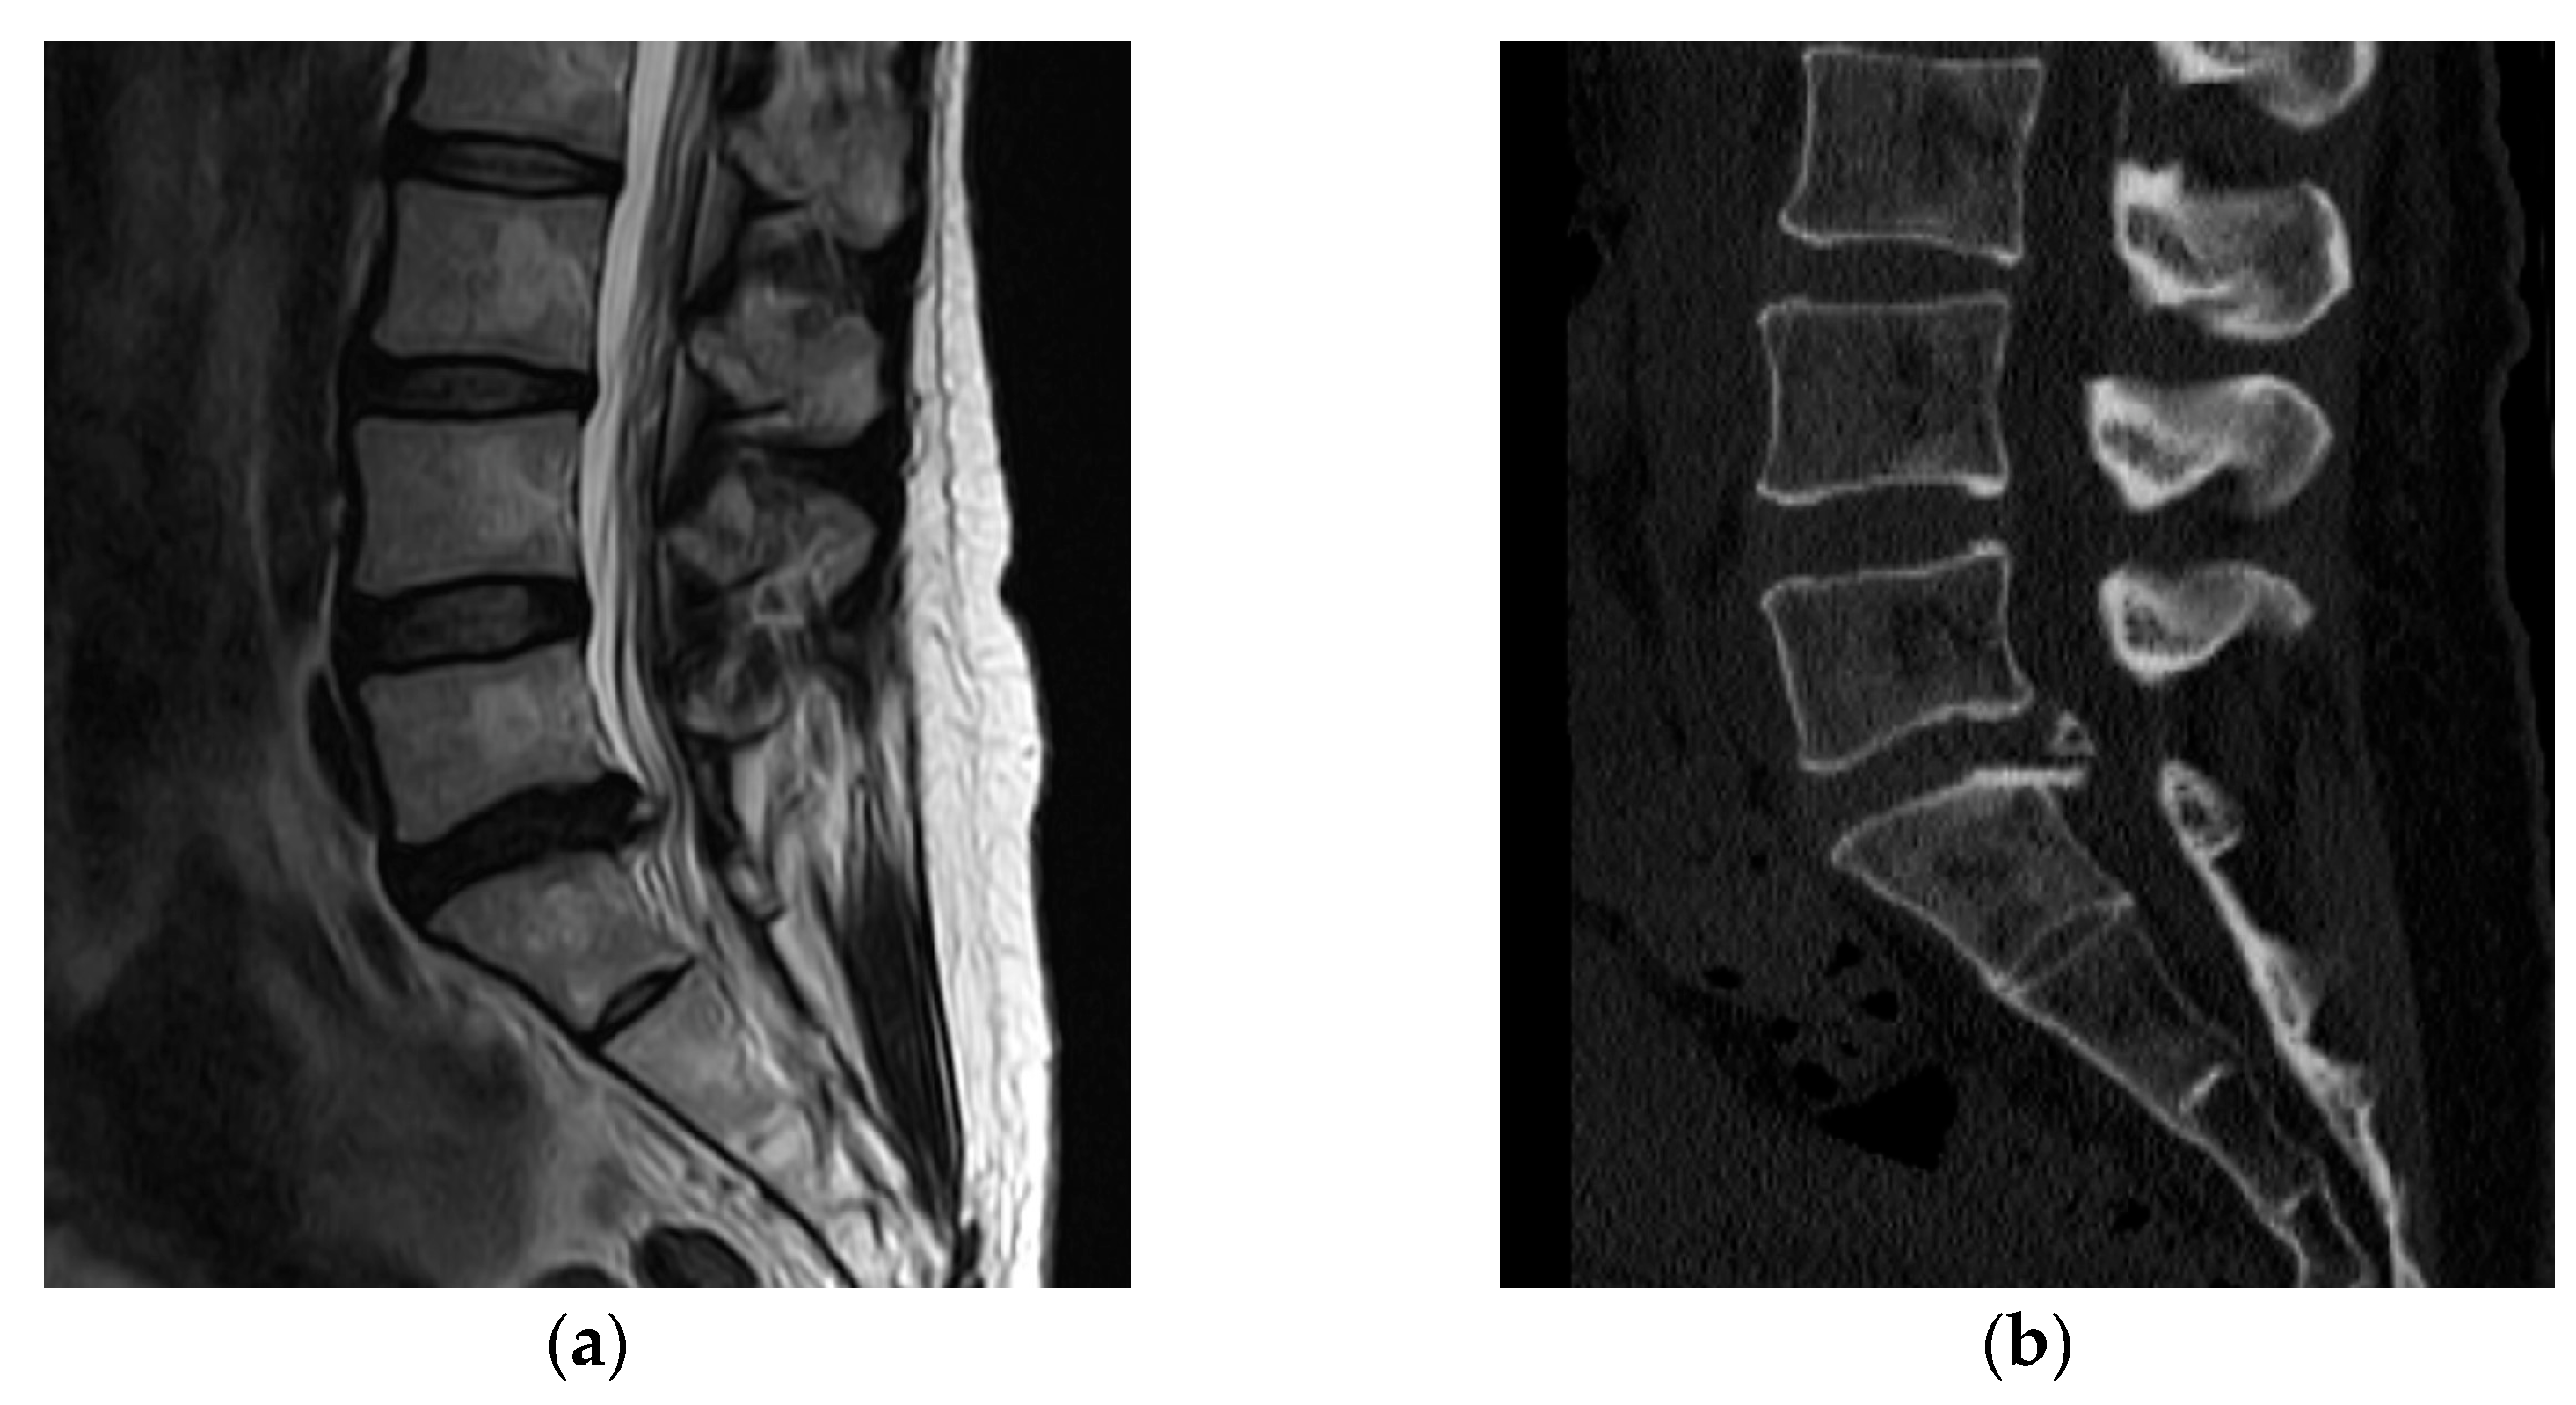

A 43-year-old woman presented to our hospital with a radiating pain in her left lower extremity. The visual analogue scale (VAS) score in her legs was 9. Magnetic resonance imaging (MRI) showed an L5/S1-level left central herniated disc. Computed tomography (CT) revealed combined posterior ring apophysis fracture at the same level (Figure 1). Conservative management did not work; therefore, she underwent microscopic discectomy. Postoperatively, she was discharged uneventfully, with improvements in the radiating pain.

Figure 1.

A 43-year-old woman presented with a radiating pain in her left lower extremity. (a) Magnetic resonance imaging (MRI) showed left central herniated disc at the L5/S1 level. (b) Computed tomography (CT) revealed a combined posterior ring apophysis fracture at the same level.